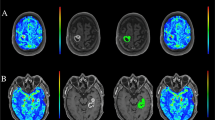

The technique of DSC-MRI relies on the susceptibility induced signal loss on T2*-weighted sequences, resulting from the passage of a bolus of gadolinium-based contrast agent. The most commonly used DSC parameter is Cerebral Blood Volume (CBV) which can be estimated [8, 9] and computed [10] based on the negative enhancement integral. Other parameters include Cerebral Blood Flow (CBF), Mean Transit Time (MTT) and Time To Peak (TTP) (Fig. 1). The estimated value of the area under the attenuation curve is proportional to the CBV but does not yield an absolute measurement. Therefore, the measurement is expressed relative to a standard reference, usually the contralateral white matter (relative CBV ratio: rCBV ratio) [11]. Overall, the rCBV ratio is an indicator of hypervascular regions and serves as the most robust parameter in DSC MRI [12].

Exemplary images of DSC-MR perfusion images. First panel shows a multicompartimental glioma (WHO grade IV) located in the left hemisphere with known irregular enhancement located in the left temporal occipital and frontal lobes. The lesion contains areas of central necrosis and shows focally increased perfusion. Second panel shows status after resection of a glioma (WHO grade IV) located in the left frontal lobe. At this level, no residual tumor is observed on the derived perfusion images. A DSC-MR perfusion imaging source data; B CBF map; C CBV map; D TTP map; E Schematic representation of image; F DSC-MR perfusion imaging source data; G CBF map; H CBV map; I TTP map; J Schematic representation of regions. DSC-MRI = dynamic susceptibility contrast magnetic resonance imaging; CBV = cerebral blood volume; ICC = intraclass correlation coefficient; CBF = cerebral blood flow; TTP = time-to-peak; WHO = World Health Organization